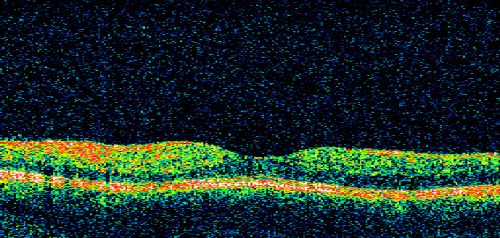

Non-Ischemic Central Retinal Vein Occlusion in Young Man (30 years) - Many Cotton Wool Spots

30-year-old man with a history of a central retinal vein occlusion for which he was first examined on 2 months ago and his vision then was 4/200.  He responded nicely to two Avastin treatments. OD is 20/20, OS is 20/60